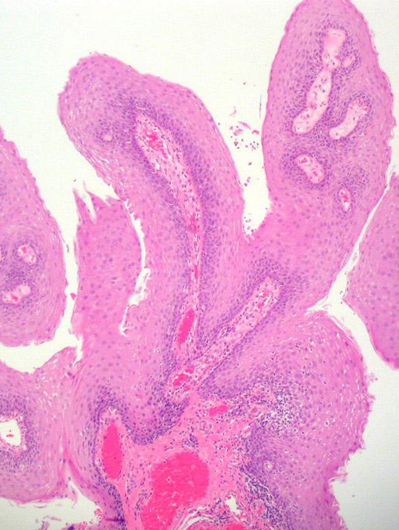

HPV感染后导致细胞增生呈现“乳头状”突起

今天一位年轻男士带着他妻子的宫颈检查报告与病理切片来会诊。原医院病理诊断为:“宫颈HSIL”,以及快发展到宫颈癌了,建议做宫颈锥切手术。我看完病理切片后发现不够“HSIL”,而是“人乳头状瘤病毒HPV”感染引起的子宫颈炎症性病变。既不需要手术,也不用担心现在有癌的危险。只需要抗HPV治疗即可。